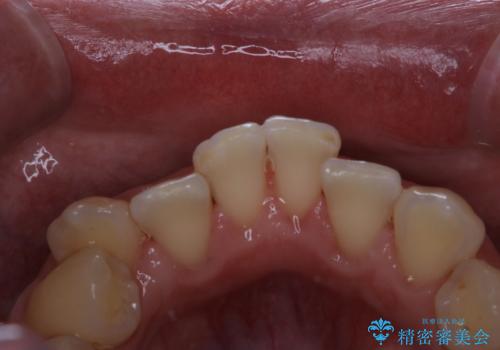

タバコのヤニをPMTCできれいに

- タバコによる着色が気になるため、全て取りたいとのことで来院されました。PMTC60分コースを行いました。

PMTCは、歯に付着した汚れを除去していくため、着色が気になる場合にも行うことができます。ご自身でのセルフケアだけで着色を落とそうとすると、逆に歯を傷つけてしまったり、精密に汚れを除去できないこともあります。また、日常生活で着色しやすい飲食物を避けたりすることはストレスに感じてしまったり、あまり現実的ではありません。

歯科医院にて、適切な処置を行うことで、長期的に安定したお口の環境が作られます。まずはカウンセリングなどもおススメです。